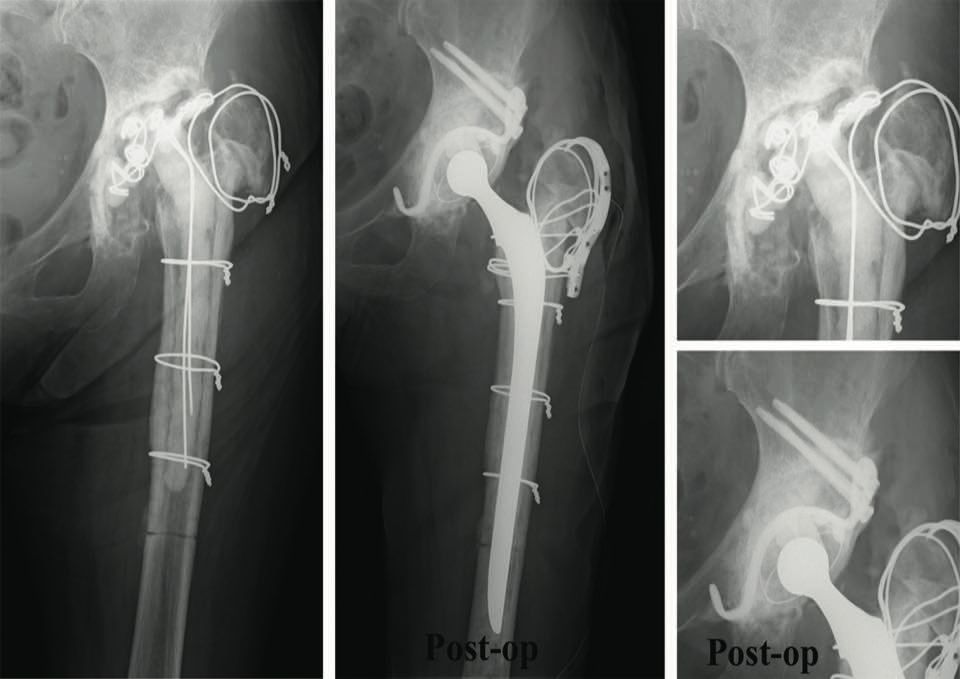

The video demonstrates the technique for reconstructing the acetabulum using an allograft and KT device (Fig. 16). It shows a two-stage revision hip replacement due to an infection. The bone defect was classified during the preoperative planning as AAOS III (combined defect).

Figures 17 and 18 show the preoperative x-rays and 3D CT images. The acetabulum was reconstructed using a KT cross and allografts.

The segmental and cavitary defects were successfully filled. Figures 19 and 20 show the postoperative images.